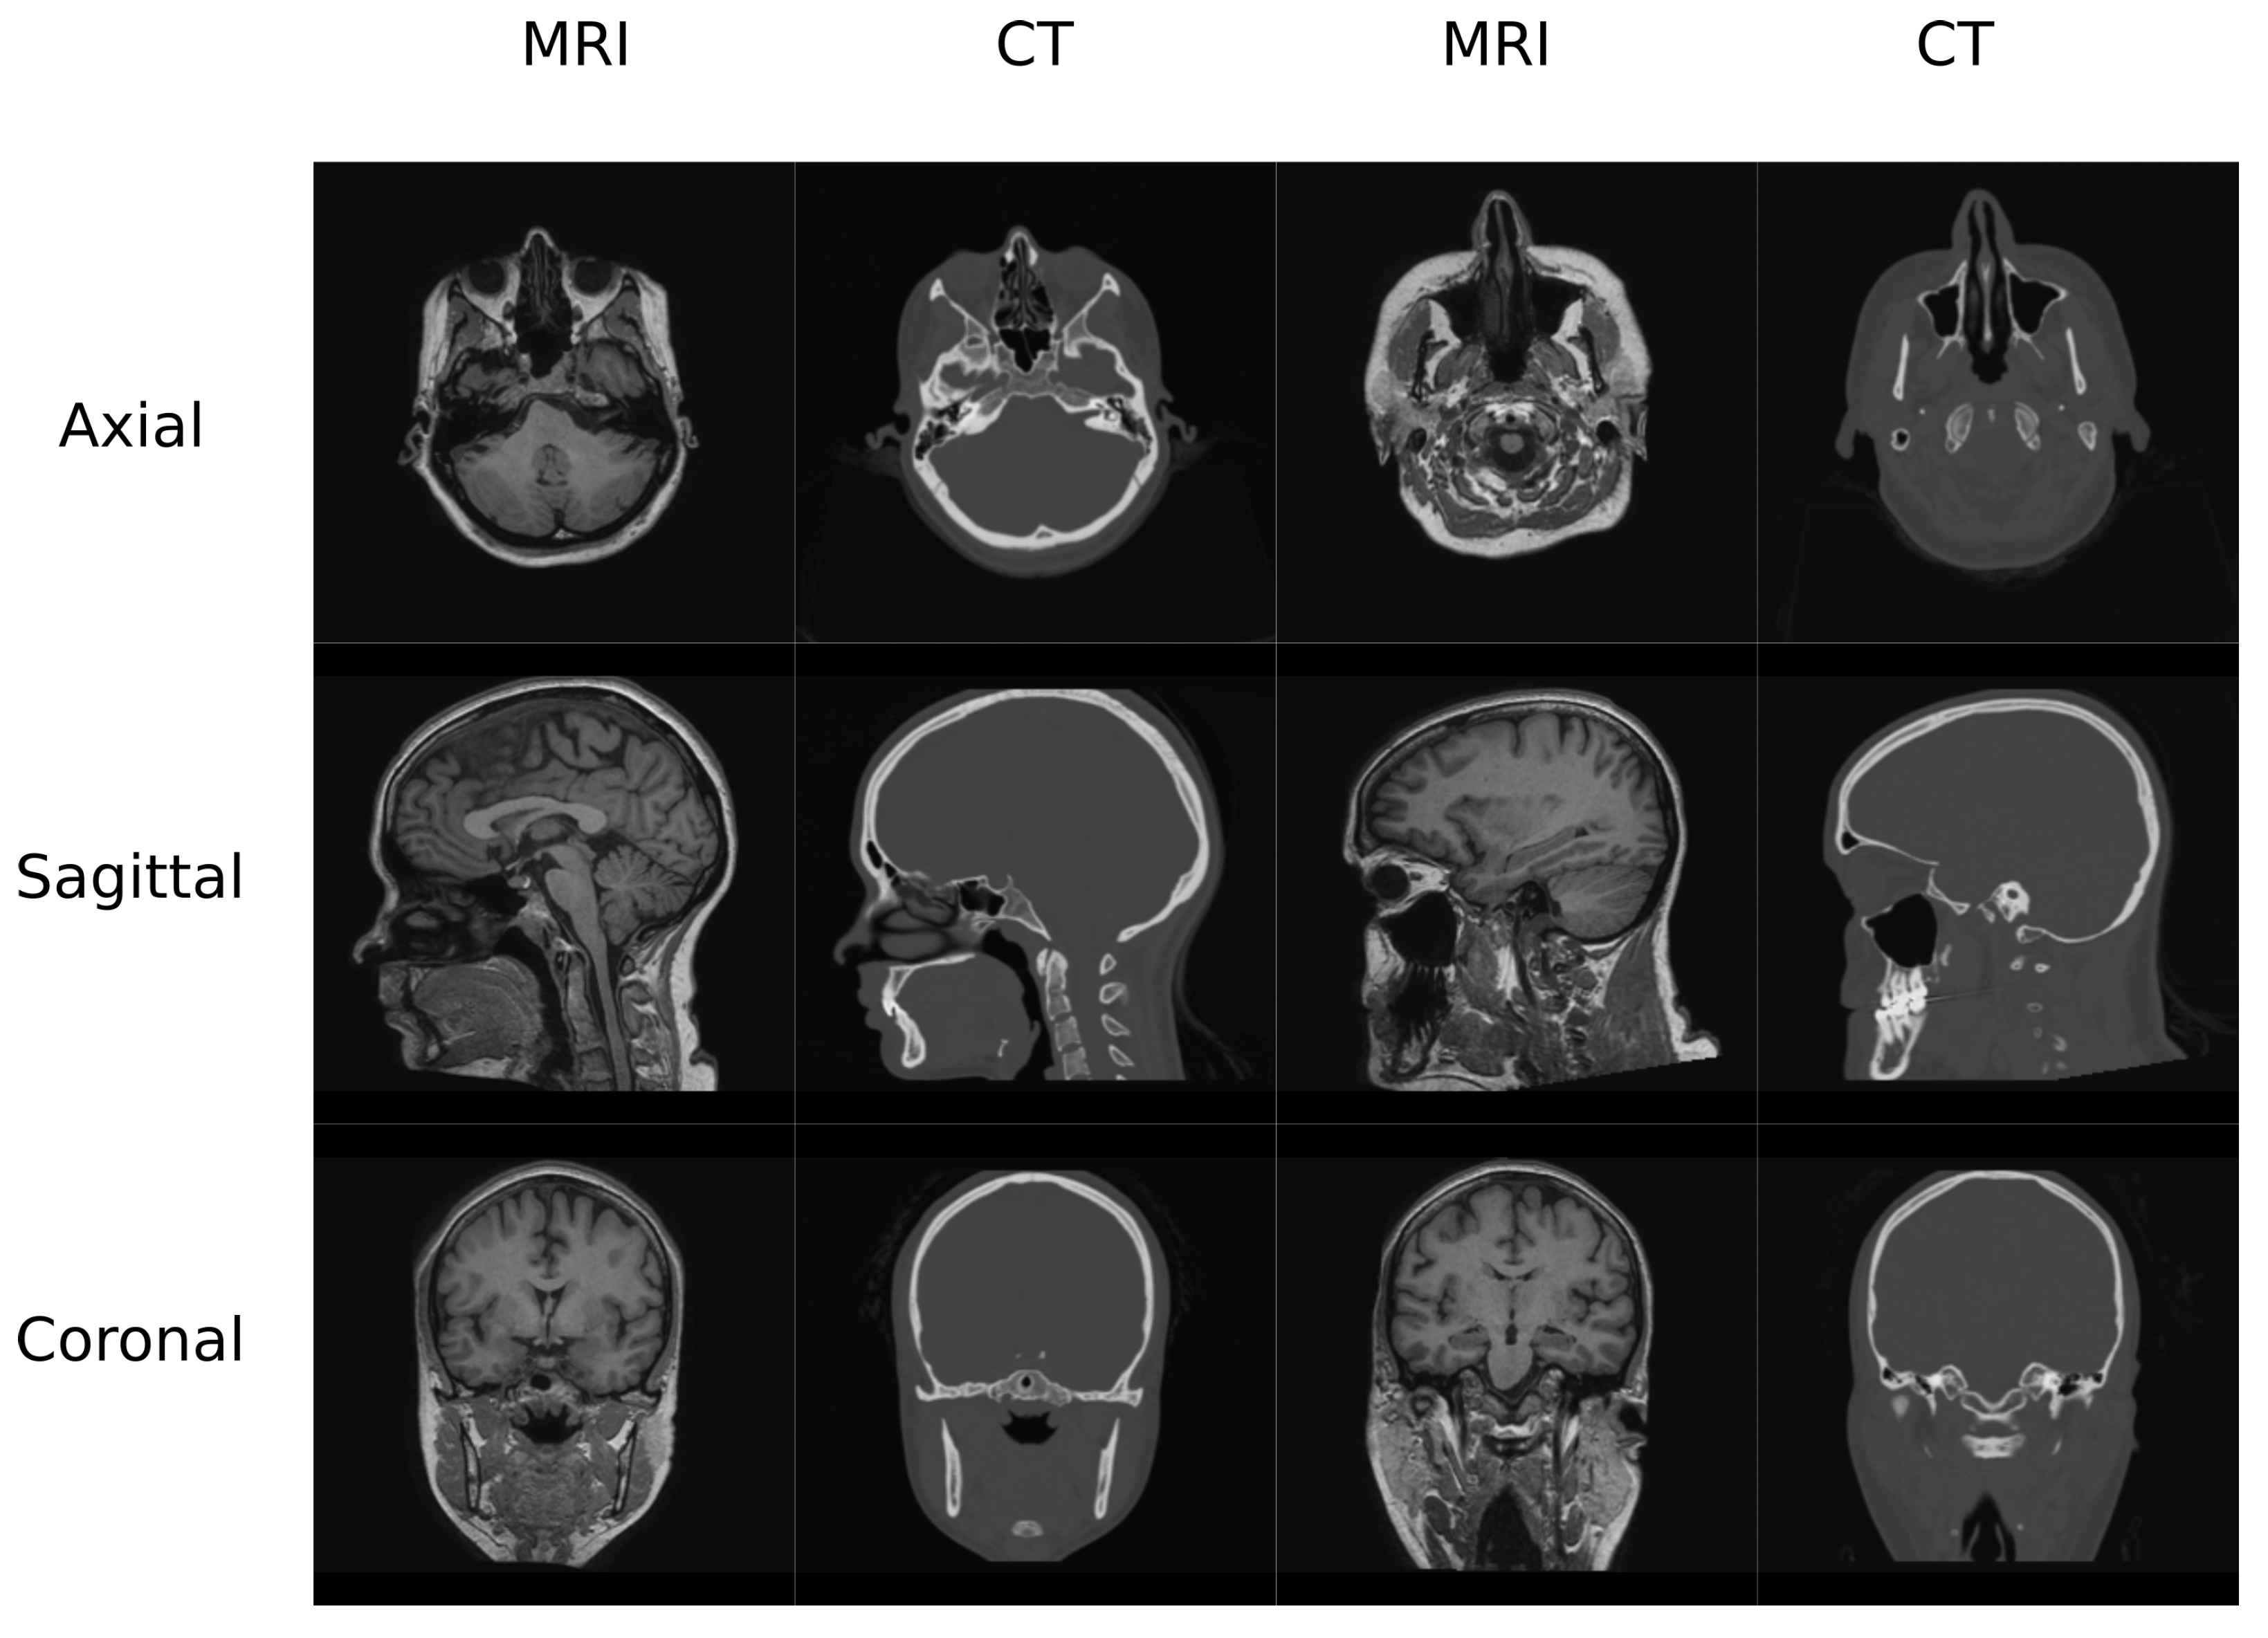

In this work, two datasets were used to train and test the different architectures that are reviewed. The first one (Figure 1) contained MR and CT head pairs from 19 healthy women (34.96 ± 5.23 y/o). MR images were acquired on a GE Signa HDxt 3.0-T MR scanner, and imaging was performed using a 3D T1-weighted sequence with a repetition time of 10.024 ms, echo time of 4.56 ms, inversion time of 600 ms, 1 excitation acquisition matrix of 288 × 288 , isotropic 1 mm resolution, and a flip angle of 12°. Low-dose CT images were acquired on a Siemens Somatom Sensation 16 CT scanner with a matrix of 512 × 512 , resolution of 0.48 × 0.48 mm, slice thickness of 0.75 mm, pitch of 0.7 mm, acquisition angle of 0°, voltage of 120 kV, and radiation intensity of 200 mA.

The second database (Figure 2) contained MR and CT images from the pelvis of 13 colorectal and 6 prostate cancer patients (61.42 ± 10.63 y/o, mean BMI 22.3 ± 2.88, 12 males/8 females). Additionally, images from follow-up visits for 9 of the colorectal cancer patients were also included in this study. MR and CT scans were performed on the same day with an average delay of 66 min. CT images were acquired on a Discovery PET/CT 710 scanner (GE Healthcare) with a matrix of 512 × 512 , resolution of 1.37 × 1.37 mm, slice thickness of 3.75 mm, pitch of 0.94 mm, acquisition angle of 0, voltage of 120 kV, and radiation intensity of 150 mA. MR data were acquired on a Biograph mMR scanner (Siemens Healthineers, Erlangen, Germany). The sequence was a dual echo Dixon-VIBE, which is the standard image for attenuation correction purposes. Dixon-Vibe acquisitions are composed by 4 sets of images: water, fat, in-phase and out-of-phase.

2.2. Preprocessing

The head database was preprocessed using 3D Slicer built-in modules [32,33]. The preprocessing pipeline included bias correction using the N4 algorithm, rigid registration to align the MR-CT patient pairs as well as to align all the patients in the same orientation, and histogram matching of the grayscale values. Finally, volumes were cropped to 256 × 256 slices in the axial direction since it is easier to have a dimension which is a power of 2 in deep learning applications. This occurs due to the network operations, which half and double the spatial dimensions of the input. Figure 1 depicts examples of the volumes in this database.

The preprocesing pipeline of the pelvis dataset was composed by a bias correction performed using the N4 module in 3D Slicer followed by an intra-subject rigid and non-rigid registration using SPM8. This step is required because the pelvis is a non-rigid region and the positioning of the subject was different for the CT and MR acquisitions. The volumes were resliced and cropped to a fixed FOV of 50 × 50 × 50 cm with 2 × 2 × 1 mm of voxel size to ensure matrix and voxel homogeneity among subjects. This step allows to prepare the images to be suitable for the DCNN by reslicing the data to 256 voxels in the axial direction. Figure 2 shows an example of the Dixon-VIBE sequence and the corresponding CT.

Figure 1. Head Data set example.

Figure 2. Pelvis Data set example.